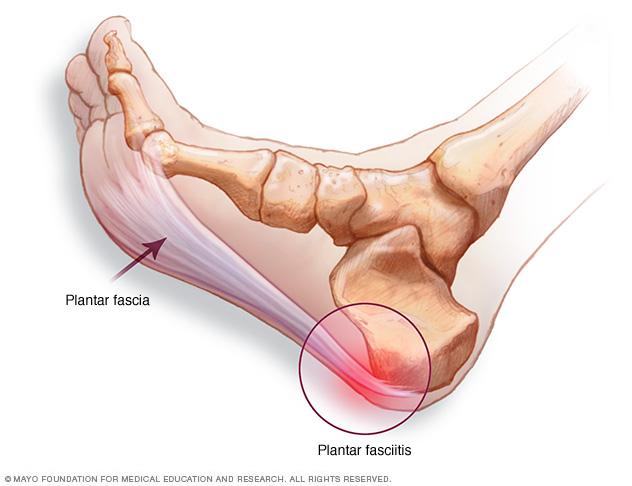

The Signs of Achilles Tendinitis Sydney Heel Pain new arrivals, Heel Pain Causes Treatment and Prevention new arrivals, Sharp Pain in the Achilles Tendon Causes Best Treatment new arrivals, Achilles tendinitis Information Mount Sinai New York new arrivals, Achilles Tendonitis Treatment in Gilbert Scottsdale Chandler Mesa Phoenix new arrivals, Achilles Tendon Tear Kenneth Bramlett MD new arrivals, Know the Symptoms of Achilles Tendonitis Tendinopathy Gait Happens new arrivals, What Causes Pain In Back Of Heel Tendon Injury Symptoms new arrivals, Achilles Tendon Pain and Injury Treatment in Chatswood new arrivals, Achilles Tendon Pain Causes Treatment Sydney Heel Pain new arrivals, Achilles Tendinopathy Kintec Footwear Orthotics new arrivals, Fast Effective Relief for Achilles Tendon Pain Manchester Burnley new arrivals, Common Conditions Causing Heel Pain new arrivals, Insertional Achilles Tendinopathy Sussex Foot And Ankle Clinic new arrivals, Achilles Tendinitis Symptoms Treatment new arrivals, Achilles tendon sharp clearance pain new arrivals, Severs Disease Sever s Disease Treatment Sydney new arrivals, Sharp Pain in Foot Causes Symptoms and Treatments Modern Foot Ankle new arrivals, Achilles Tendonosis and Tendonitis Achilles Tendonosis and Tendonitis Chiropractors for Chandler Sun Lakes and Ocotillo Arizona new arrivals, Heel Pain Bunbury Foot Ankle Surgeon new arrivals, Achilles Tendon Pain Causes Treatments Prevention new arrivals, What Can Cause Sharp Stabbing Foot Pain new arrivals, Protecting Your Achilles Heel From Injury Dr Gordon Slater new arrivals, Pain In The Back Of The Heel What Could It Mean new arrivals, Plantar fasciitis Altru Health System new arrivals, Spink Physiotherapy Achilles tendon pain Achilles tendon pain often occurs due to overuse sudden increased intensity of physical activity poor footwear tight calf muscles improper warm up inadequate r... new arrivals, Pain at the back of the heel How to figure out what s causing it and what to do about it new arrivals, 4 Heel Pain Symptoms to Take Seriously Chicagoland Foot and Ankle Board Certified Foot and Ankle Specialists and Surgeons new arrivals, Sharp Pain in the Achilles Tendon Causes Best Treatment new arrivals, Ankle Pain Causes Treatment Northeast Spine and Sports Medicine new arrivals, Achilles Tendinitis Ankle Pain Foot Injury new arrivals, Achilles Tendonitis Causes Symptoms Signs Gleneagles Hospital new arrivals, Pain at the back of the heel How to figure out what s causing it and what to do about it new arrivals, Achilles Tendonitis Vs Plantar Fasciitis Which Do I Have new arrivals, Achilles Tendon Pain Symptoms Causes Treatment Exercises new arrivals.

Achilles tendon sharp stabbing pain new arrivals